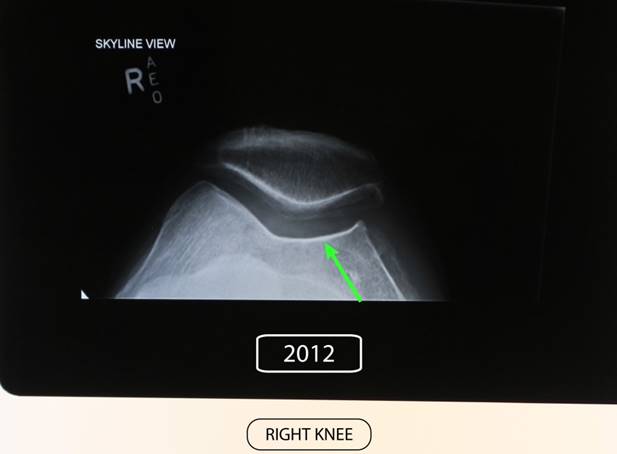

OSTEOARTHRITIS and OSTEOPOROSIS.

Before Stem Enhance ULTRA.

After Stem Enhance ULTRA.

81 Year old with Pre-existing Osteoarthritis and Osteoporosis

Before commencing supplementation he was seeing a specialist preparing for knee replacement.

Taken Stem Cell Nutrition for 7 months. 2 capsules of StemEnhance ULTRA in the morning and again 2 StemEnhance ULTRA at night.

Had another xray taken 7 months later and following this period of supplementation he was advised by the specialist that he no longer required a knee replacement as all the cartlidge had grown back and the bone density repaired. (See the green arrow area on both pictures.)